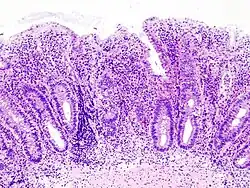

H&E stain of a colonic biopsy showing a crypt abscess, a classic finding in ulcerative colitis

Biopsies of the mucosa are taken during endoscopy to confirm the diagnosis of UC and differentiate it from Crohn's disease, which is managed differently clinically. Histologic findings in ulcerative colitis include: distortion of crypt architecture, crypt abscesses, and inflammatory cells in the mucosa (lymphocytes, plasma cells, and granulocytes).[28] Unlike the transmural inflammation seen in Crohn's disease, the inflammation of ulcerative colitis is limited to the mucosa.[28]